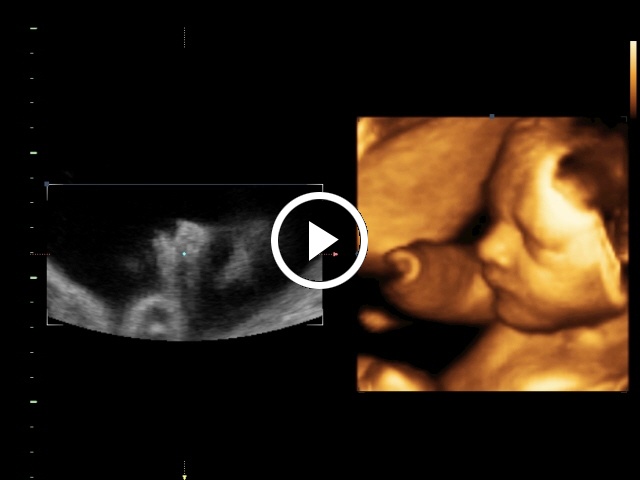

3. 4D-mód Cine képei